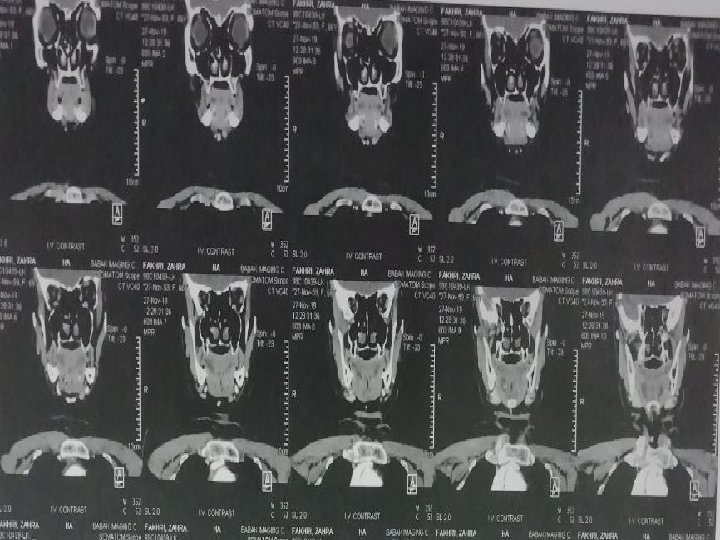

CT Scan axial of neck with and without IV Contrast 98/6/9